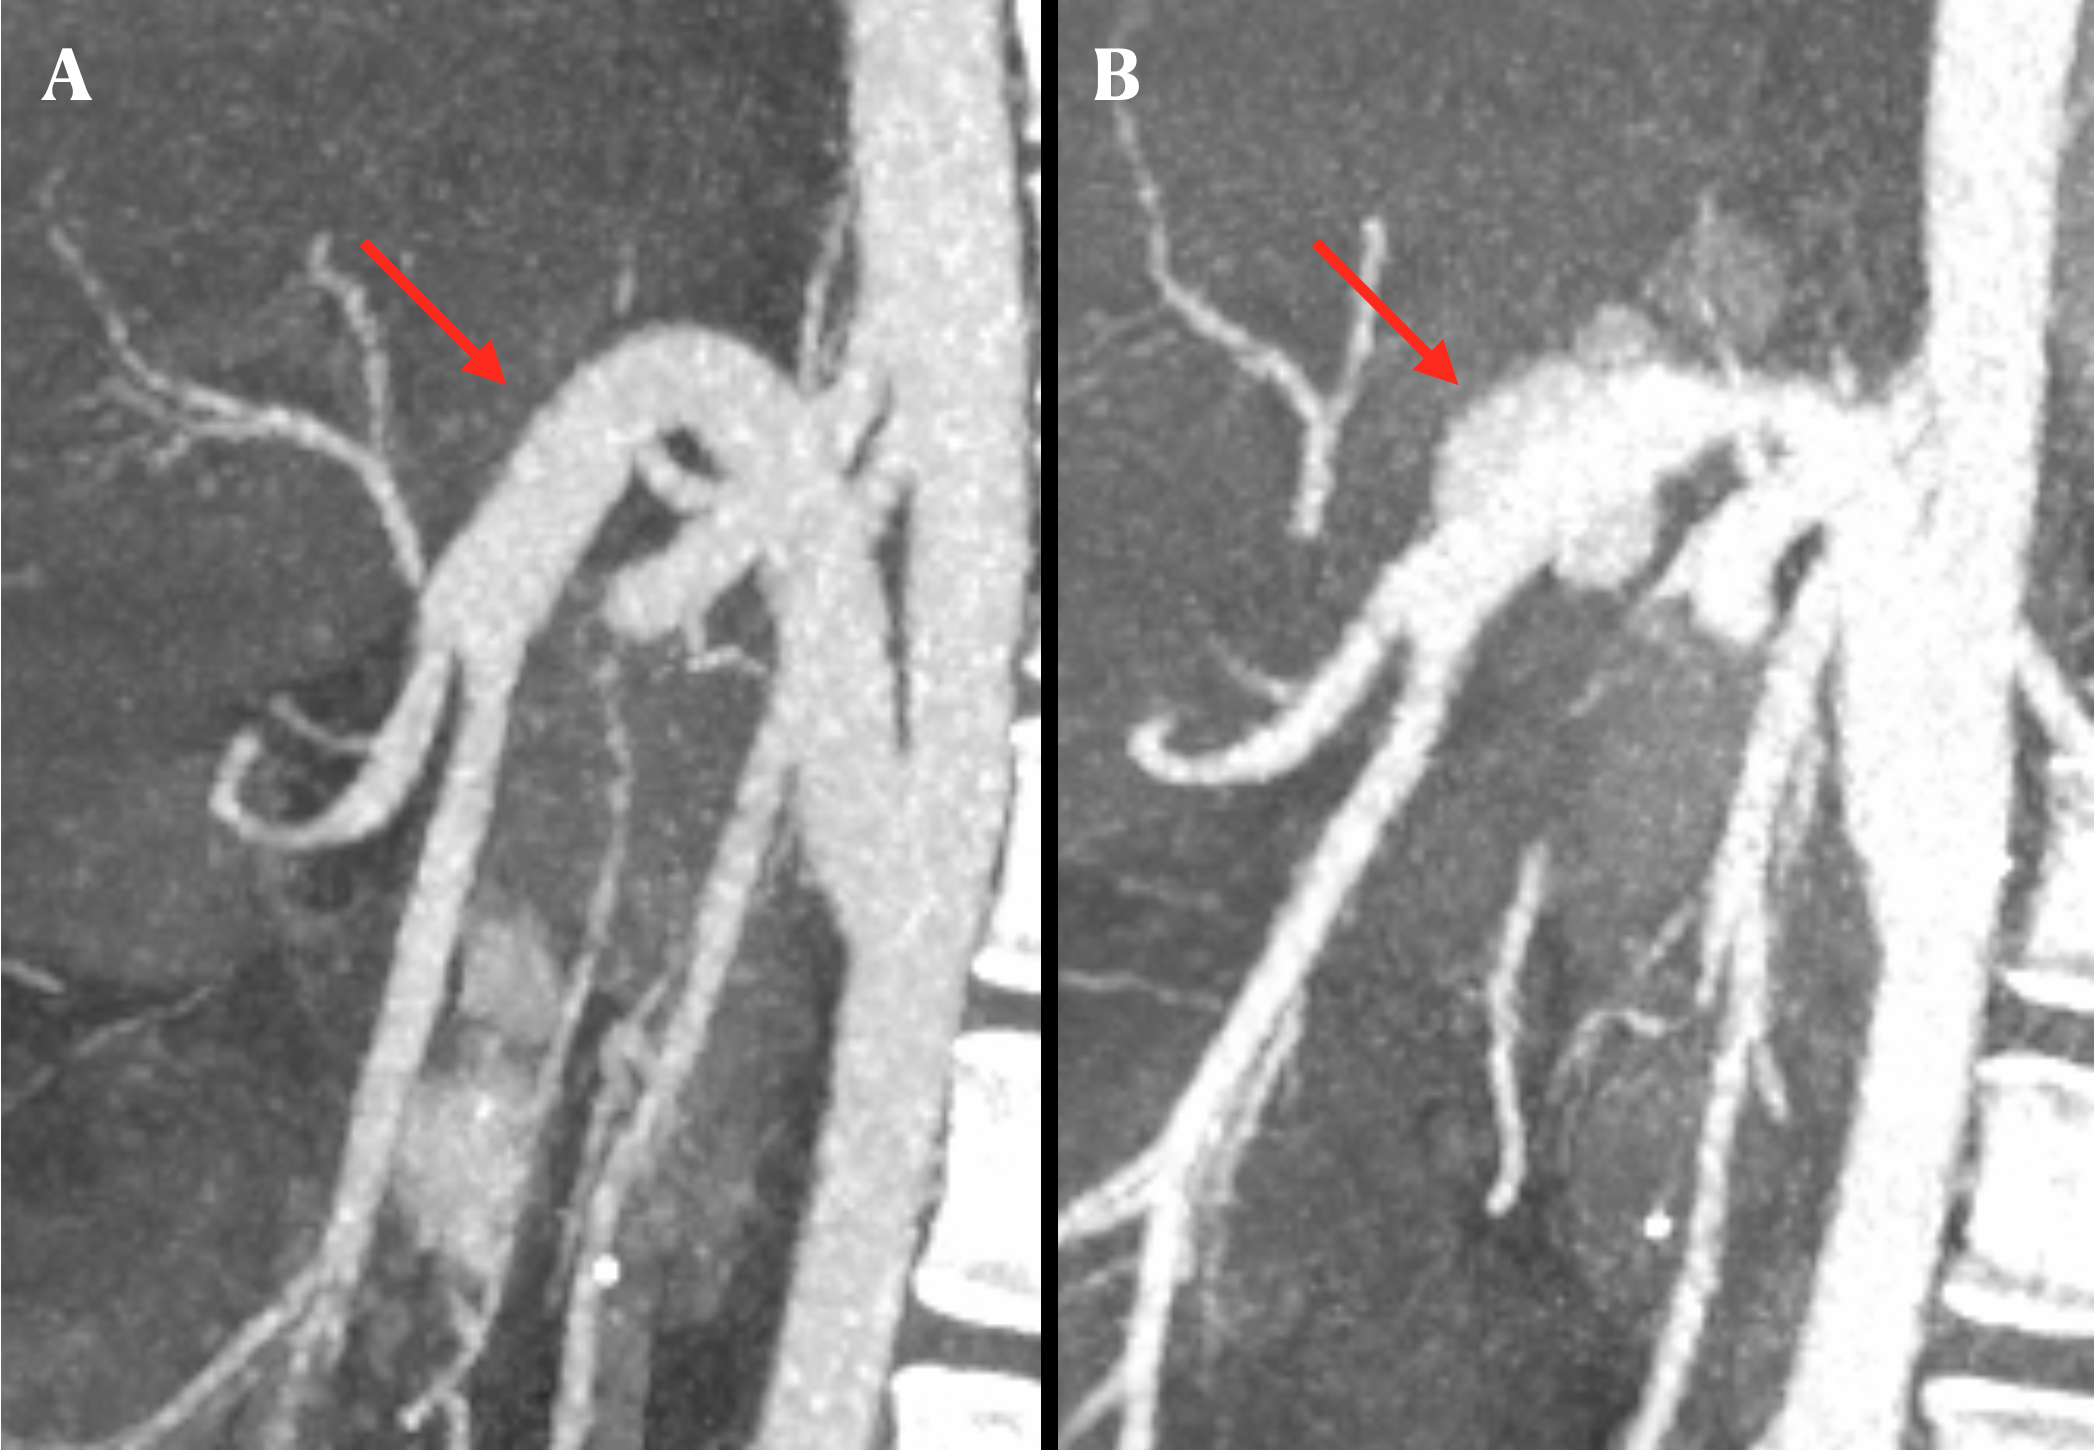

Results: Out of 156 ITx performed, six patients (3.8%) experienced eight episodes of MA. Among them, four patients received a multi-visceral transplant, while two underwent a liver-small bowel transplant, all vascularised with infra-renal aortic conduits. The median age at MA diagnosis was 36.5 years (range 24-70), occurring bimodally either early post-transplant (2, 3, 6, 8 weeks) or in a later phase (55, 377 weeks). Two patient experienced recurrence, occurring on average 132.4 weeks from the initial diagnosis (range 69.6-195.3). A history of hollow viscus perforation or anastomotic leak after transplant was identified in all cases except one (83.4%). Diagnosis was made peri-operatively in two cases (33.3%) due to ruptured aneurysms necessitating urgent laparotomy, while the remaining cases were diagnosed via angio-CT (Figure 1), typically in the context of abdominal pain and ongoing sepsis.